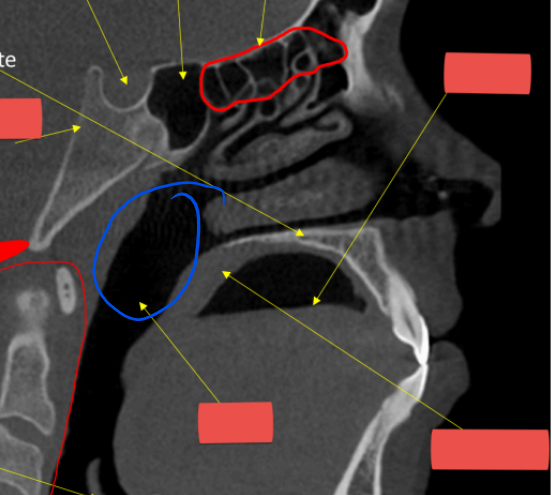

hyoid

hard palate

anterior nasal spine